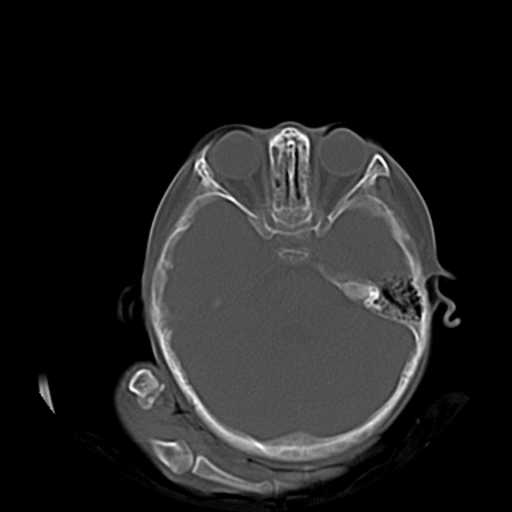

2.左侧上颌窦后壁部分骨质缺损,内有一牙齿样高密度,周围似乎无明显囊肿形成(没有继续往下扫描,而且只有骨窗,不便观察)。暂考虑左侧上颌窦牙源性囊肿可能。

3.小脑以及右侧颞叶无明显异常,颅盖以及颅底诸骨未见明显骨折,双侧枕骨内板蛛网膜粒压迹多、略深。

右侧颅底后可疑颅窝骨折.

双侧双颌窦及筛窦内可见密度增高影,考虑付鼻窦炎,上颌窦后壁骨折.